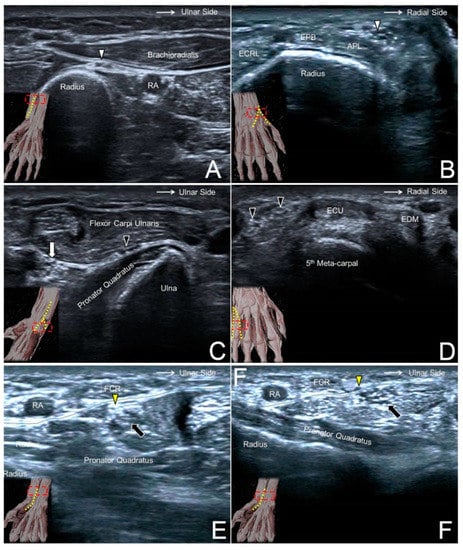

Figure 3. A snapped medial antebrachial cutaneous nerve (black arrow) in a woman complaining of forearm pain (A). A swollen lateral antebrachial cutaneous nerve (big white arrow) compared to the nerve of the asymptomatic side (small white arrow) in a woman with forearm pain (B). A lateral antebrachial cutaneous nerve (dotted circle) entrapped by the distal biceps tendon during elbow supination/pronation (C). A posterior antebrachial cutaneous nerve (yellow arrowhead) with peripheral hypervascularity in a male with chronic lateral epicondylitis (D). A swollen superficial radial nerve (big black arrowhead) compared to the nerve on the asymptomatic side (small black arrowhead) in a man with de Quervain’s tenosynovitis (E). A neuroma of the dorsal ulnar cutaneous nerve (big white arrowhead) and the normal contralateral nerve (small white arrowhead) in a man with a fracture of the 5th metacarpal bone (F). UN, ulnar nerve; BT, biceps tendon; CET, common extensor tendon of the wrist; ECRL, extensor carpi radialis longus muscle; APL, abductor pollicis longus tendon; EPB, extensor pollicis brevis tendon; ECU, extensor carpi ulnaris tendon.

The most common causes of MACN injury are iatrogenic, e.g., venous punctures, injections for medial epicondylitis, or cubital tunnel releases. A subcutaneous lipoma could also be the culprit of MACN entrapment [14]. Repeated flexion and extension of the elbow (like shaking a rug) could place the nerve under the risk of overstretching [15]. When scanning patients with MACN neuropathy, evoking Tinel’s sign by sonographic palpation is paramount as well as a dynamic examination of the flexed and extended elbow (Figure 3A, Supplementary Video S3). In most cases with suspicion of MACN entrapment, the nerve might not present an overt change in the sonography, and a sono-Tinel sign combined with a guided nerve block would be required to confirm the diagnosis.

5.3. Clinical Implication

The close anatomical relationship between the LACN and the cephalic vein renders the nerve vulnerable to iatrogenic injuries. Traumatic nerve injury during venipuncture is the main cause of LACN neuropathy. The nerve can be damaged by direct needle touch or compression by an adjacent hematoma/thrombosis. As the LACN is located next to the distal biceps tendon, the second most common etiology is related to distal biceps tendon tears. Another less common cause is a compression by a cast used to immobilize fractures near the elbow joint. When the LACN is injured, it typically appears enlarged in US imaging (Figure 3B), and its echogenicity might increase due to hemorrhage inside the nerve [17]. A dynamic examination (during supination/pronation of the forearm) can also contribute to the identification of problems related to distal biceps tendon-related problems (Figure 3C, Supplementary Video S4).

6.3. Clinical Implication

7.3. Clinical Implication

8.3. Clinical Implication

9.3. Clinical Implication